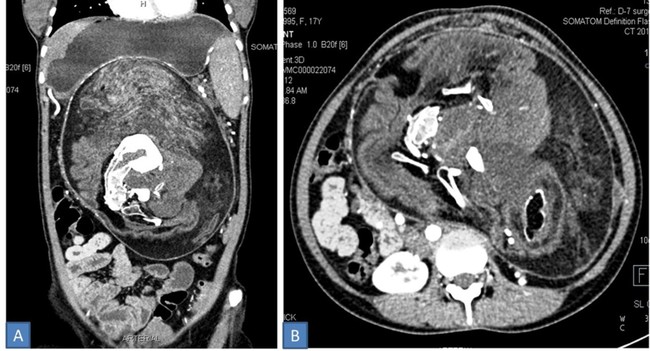

En la analítica de la joven encontraron gonadotropina coriónica beta-humana (β-HCG) y proteína alfa feto, hormonas presentes en el embarazo. También hallaron una masa abdominal de consistencia firme a dura, de superficie irregular y que no se movía con la respiración. Al realizarle una tomografía computarizada (CECT) con contraste, esta mostró una masa bien definida que al extirparla medía 30×16×10 cm.

Mostraba además áreas de densidad de grasa, tejido blando y múltiples componentes de densidad calcificada de varios tamaños y formas "que se asemejaban a la forma de vértebras, costillas y huesos largos".

Además, se descubrieron "múltiples dientes y estructuras que se asemejaban a las yemas de las extremidades". Esta masa estaba causando desplazamiento y compresión de las vísceras abdominales adyacentes.